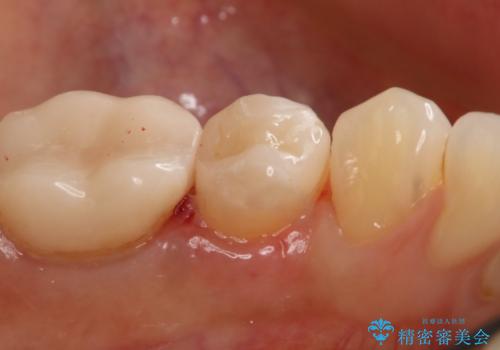

- 左下5番の銀歯をセラミックにやり変え希望の患者様です。

切削量を考慮し、セラミックインレーでの治療を選択しました。

銀歯直下のう蝕を除去しCRで裏層を行った上で、形成・印象を行っています。